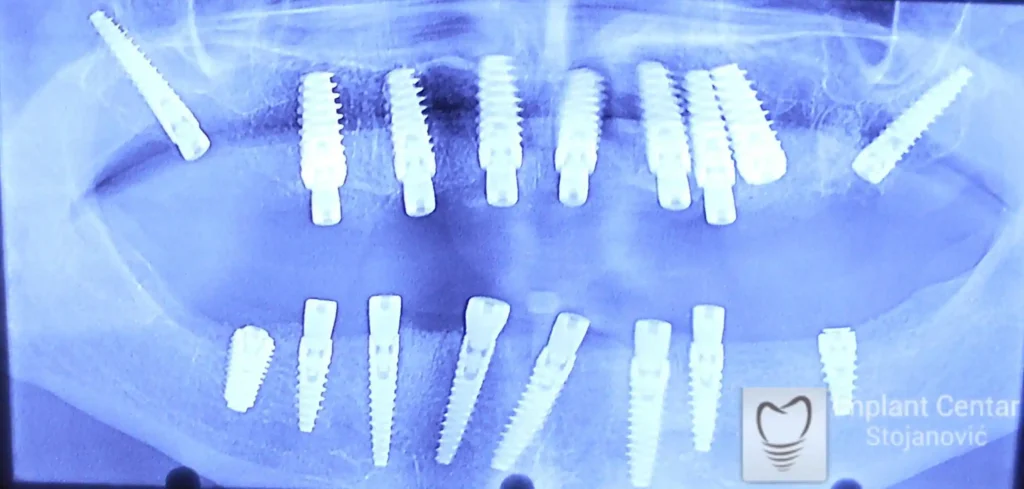

Zbog toga je plan terapije uključivao vađenje svih preostalih zuba i ugradnju implantata u gornjoj i donjoj vilici. U gornjoj vilici postavljena su i dva tuberopterigoidna implantata, kao zamena za sinus lift proceduru, što se može videti na ortopan snimku nurađenom odmah nakon ugradnje (slika 3).

Već tri dana nakon operacije, pacijent je zbrinut fiksnim privremenim zubima na implantatima, čime je odmah povraćena funkcija i estetika osmeha.

Nakon završetka perioda integracije implantata, izrađeni su cirkonijum-keramički mostovi u gornjoj i donjoj vilici (slika 6.).